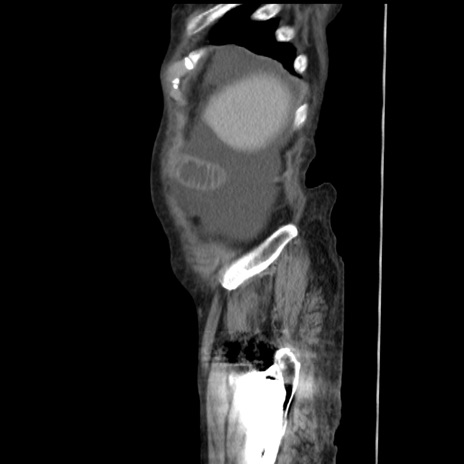

症例31(矢状断像)

【症例】80歳代 女性

【主訴】腹部膨満感

【現病歴】他院にて肝硬変にてフォロー中。1週間前から便秘、腹部膨満感、臍部腫瘤あり受診となる。

【既往歴】肝硬変

【身体所見】腹部膨隆あり、皮膚変化なし、疼痛なし。

【データ】WBC 4600、CRP 0.25